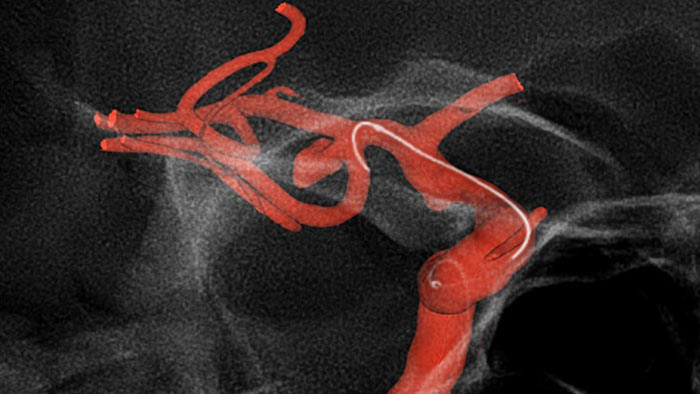

Используйте полученные ранее данные КТ- или МРТ-ангиографии и совмещайте их с данными рентгеноскопии в режиме реального времени, чтобы визуализировать границы поражения и соответствующей васкуляризации для оценки рисков. Повторное использование полученных ранее данных помогает контролировать дозу облучения и количество контрастного вещества.

Технология SmartCT Roadmap улучшает визуализацию перекрывающихся сосудов, способствуя точному управлению проводником и катетером при их проведении через сложные сосудистые структуры. Данная технология обеспечивает высокую точность операции, компенсируя при этом в режиме реального времени артефакты движения С-дуги, стола и небольших движений пациента.